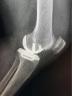

微创单髁置换手术就是微创保膝理念的有效解决办法之一。它也叫做部分膝关节置换术,手术只是将膝关节内侧部分磨坏的股骨和胫骨骨头切除,装上非常耐磨的人工材料,保留外侧未磨损的关节和关节内所有韧带。而且手术可以通过比全膝置换小得多的伤口来完成,其创伤小、出血少、恢复快、假体寿命长、功能恢复程度高等一系列优点正逐步的显示在世人眼前。

近年来,微创、保膝的理念逐渐被大家所接受。事实上,膝关节骨关节炎的主要病理机制是膝关节表面的软骨磨损、缺失而逐渐出现骨刺、肿胀、关节积液等一系列的病理变化。

很多研究结果显示,在饱受膝关节骨关节炎困扰的患者中,85%的磨损只累及膝关节内侧部分,而且这种现象随着时间的推移也基本不变,10-18年的追踪结果显示这种单纯的内侧部分磨损很少会向外侧扩展,所有这些临床上的发现,都是膝关节“前内侧骨关节炎”理论最好的佐证。

通俗来讲,绝大部分膝关节老化的患者,病变都是从膝关节内侧开始的,而膝关节的外侧软骨是完好的。针对这一部分“前内侧骨关节炎”患者,如果选择全膝关节置换术,将功能完好的外侧软骨及韧带都去掉,岂不是有些可惜吗?